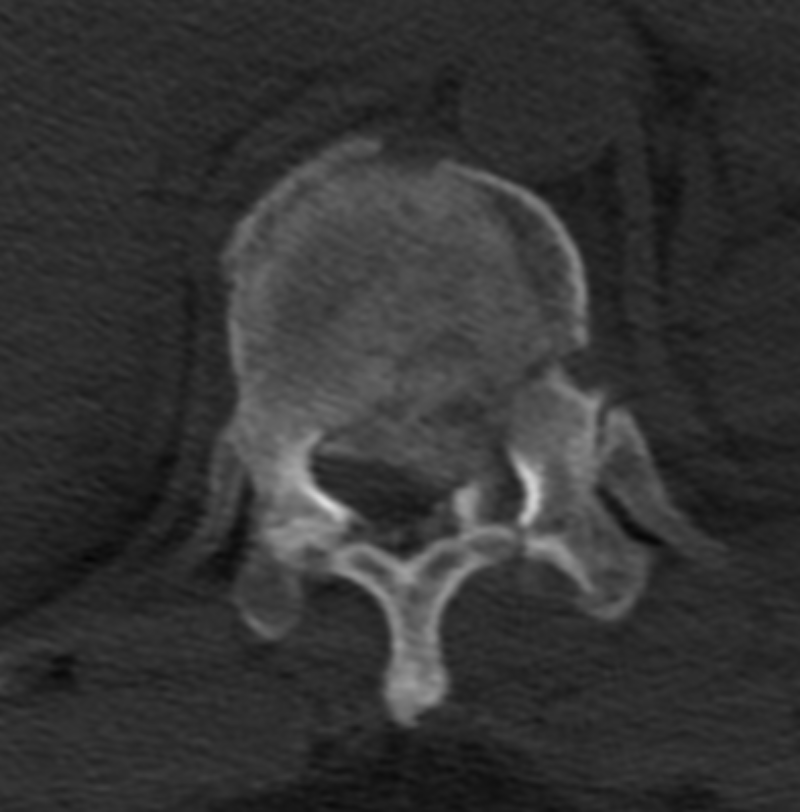

胸12椎體爆裂性骨折,骨折碎塊壓迫椎管